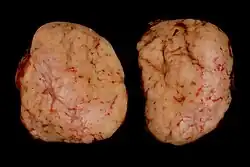

Masywne zajęcie węzłów chłonnych przytchawiczych, wnęki płuca i podostrogowych, zajęcie kręgów

Nacieki chłoniaka Hodgkina w śledzionie